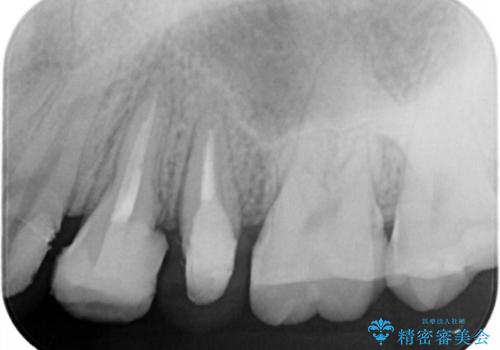

- 歯ぐきの腫れや、歯の内部が黒く見えることからの虫歯の治療を求めて来院されました。

虫歯が大きかったことから、神経の温存はできたものの歯ぐきよりも深い虫歯の問題を解決するため部分矯正治療を併用したセラミック治療を行うこととしました。

当初、歯ぐきよりも深い虫歯のぞんざいや、歯のポジションに問題がありましたがマルチブラケットを用いた部分矯正を行うことで適切な位置へと歯を移動させ、歯周環境を整えたセラミック治療を行うことができました。